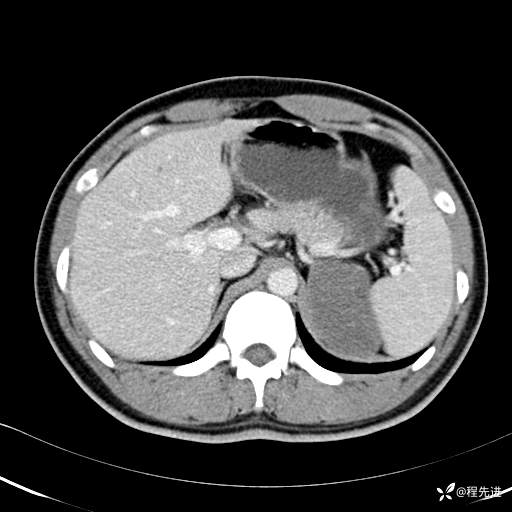

CT平扫:(CT值:平扫,27HU,动脉期,27HU,门静脉期,31HU,平衡期,32HU)

动脉期: